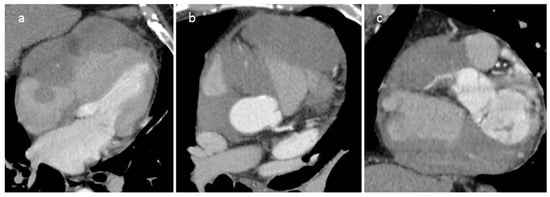

3.1. Thrombus

| Thrombus | Adulthood | LA, LAA (AF) LV (MI) | Asymptomatic, embolic events | Non-enhancing Intracardiac lesion | Acute: Low echodensity, rounded with smooth contours Chronic: High echodensity, linear or crescentic lesions along the endocardial surface | Low attenuation, no contrast enhancement, chronic thrombus may be calcified Usefulness of delayed CT imaging, as in the LAA stasis of blood can simulate a thrombus on early arterial images | Acute: hyper T1w and T2w Subacute: hyper T1w and hypo T2w Chronic: low T1w and T2w No enhancement. |